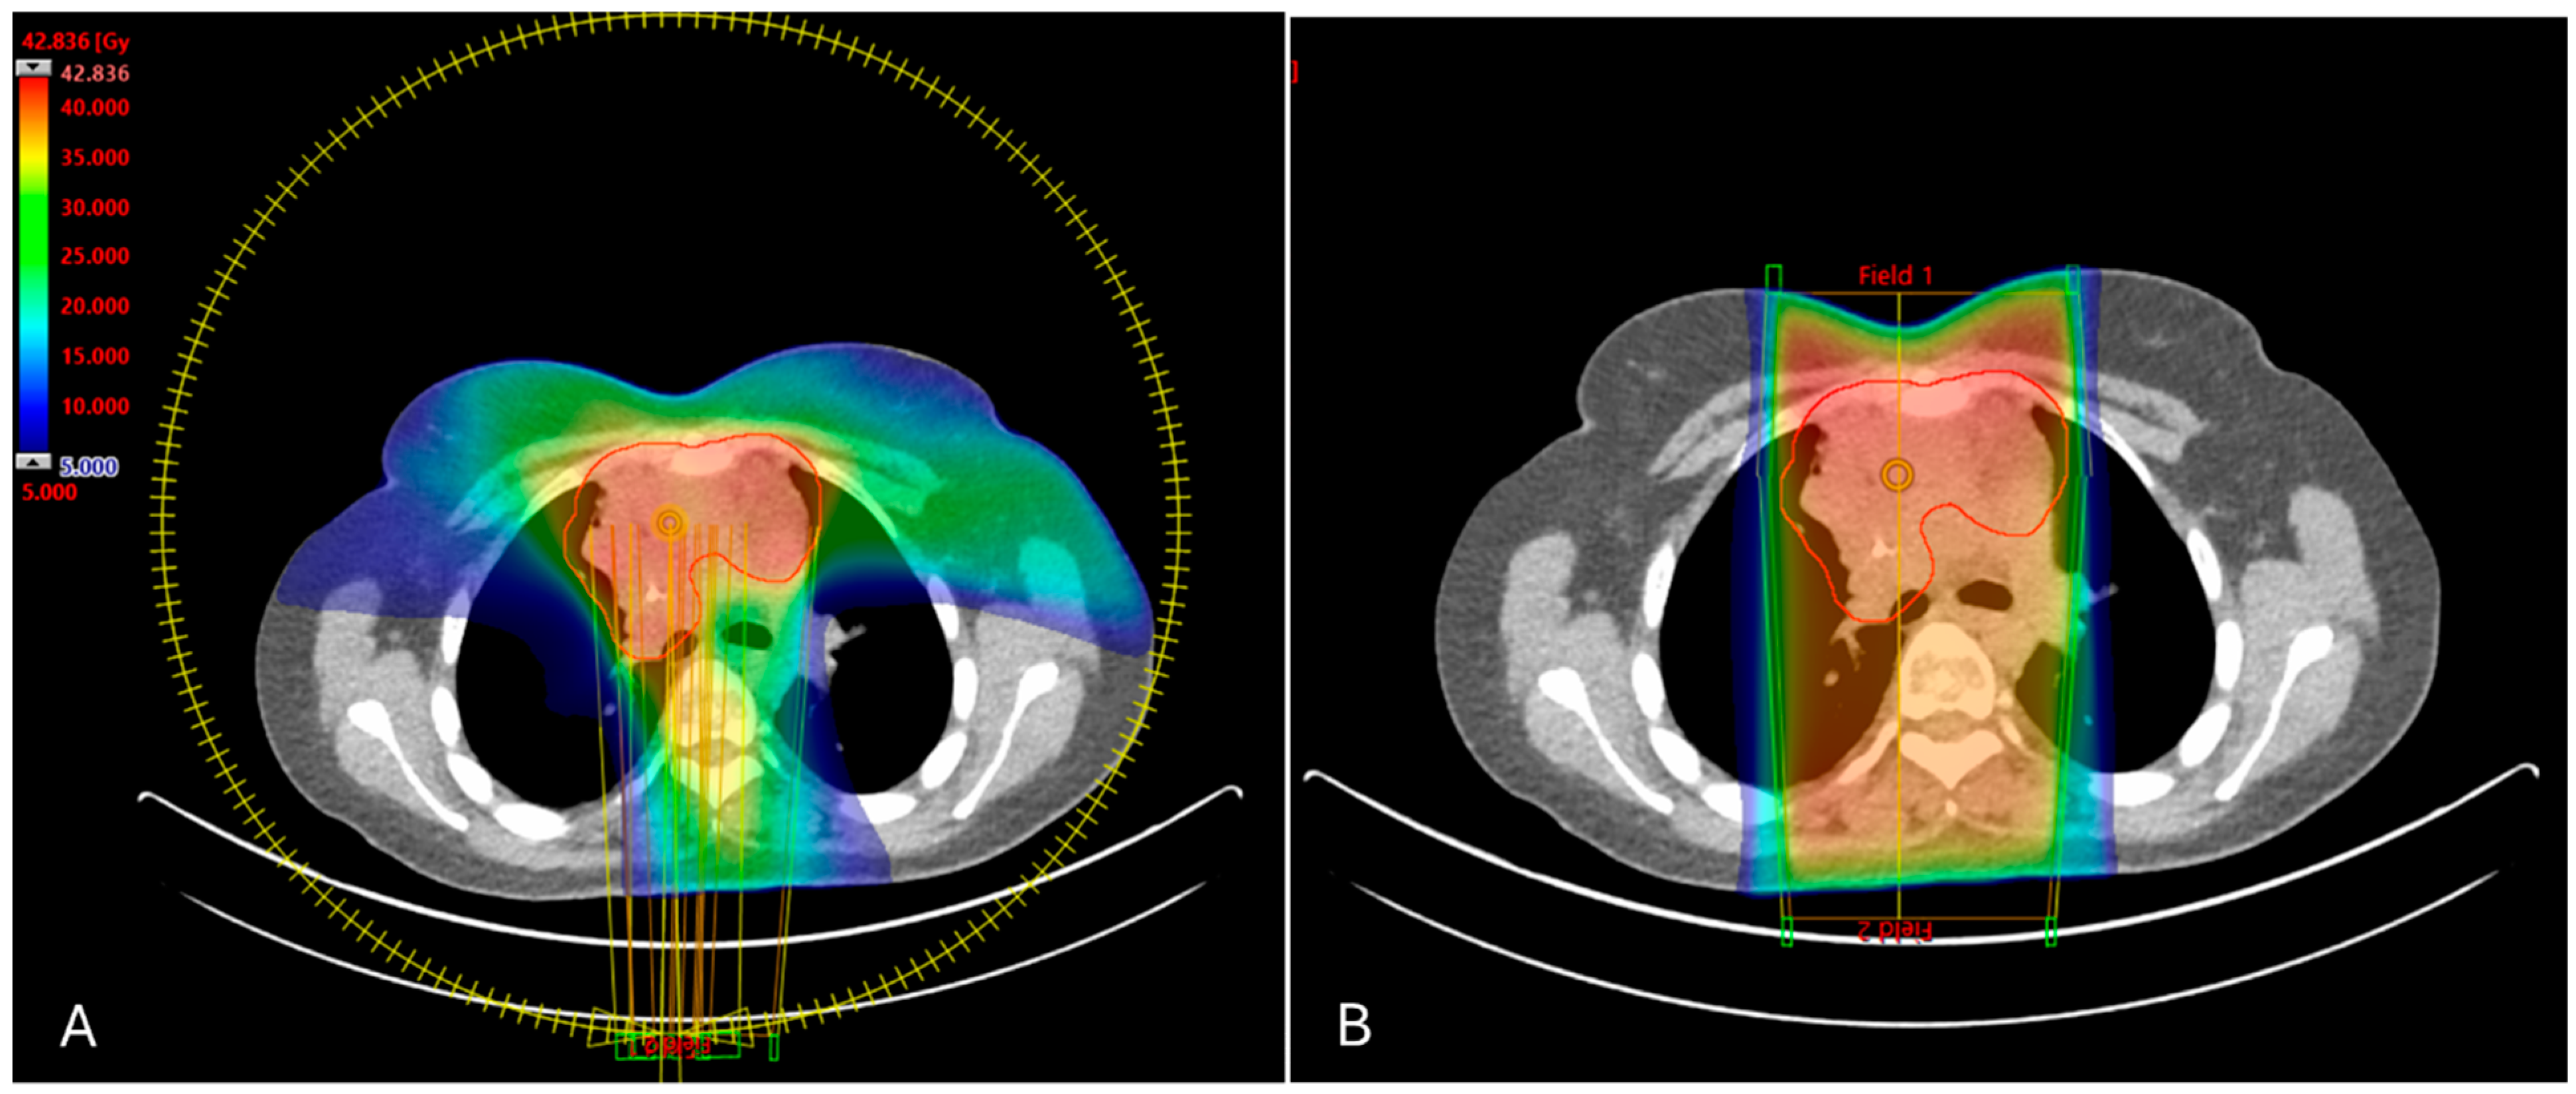

3.1. DVH Metrics